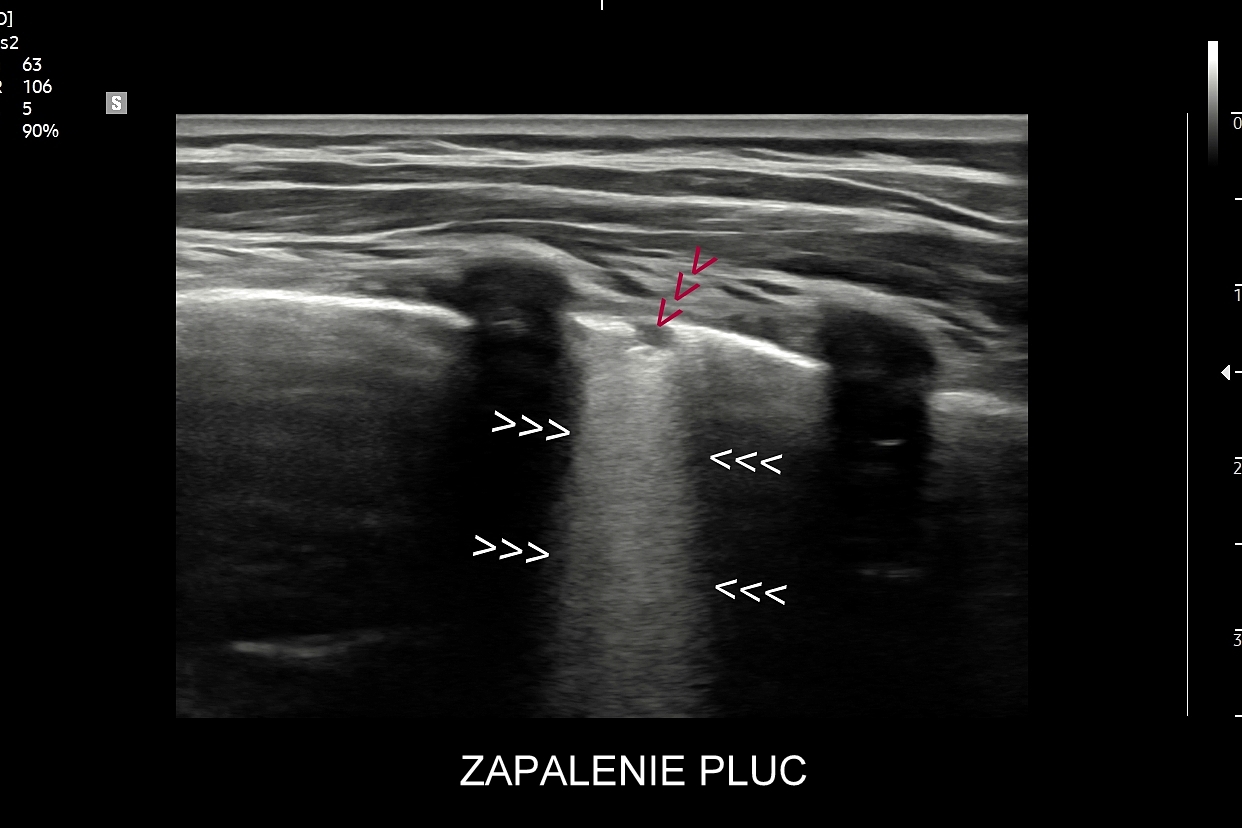

Ultrasonografia płuc oparta jest o fizykę fal akustycznych. Wychwytuje zarówno schorzenia lokalizujące się w zewnętrznych partiach płuc oraz w jamach opłucnowych w postaci realnego obrazu, ale także wykazuje istotne diagnostycznie informacje z głębszych partii narządu na podstawie specyficznych artefaktów generowanych przez patologie wewnątrz płuca.

Kluczem do wartościowego zastosowania metody USG w diagnostyce pulmonologicznej jest zrozumienie jej możliwości oraz ograniczeń. USG jest niezwykle czułym badaniem w diagnostyce zapaleń płuc zarówno płatowych, jak i atypowych, np. wywołanych przez Mycoplasma lub Chlamydia. W przypadku zapalenia płuc pojawienie się widocznych zmian sonograficznych wyprzedza wystąpienie fenomenów osłuchowych wykrywanych przy osłuchiwaniu klasycznym stetoskopem. Metoda USG jest również bardzo czuła w diagnostyce chorób opłucnej i jam opłucnowych, takich jak nowotwory opłucnej, odma odma opłucnowa czy płyn w jamie opłucnowej. W rękach doświadczonego lekarza badanie USG może być przydatne w wykryciu zatorowości płucnej, a nawet guzów nowotworowych płuc.